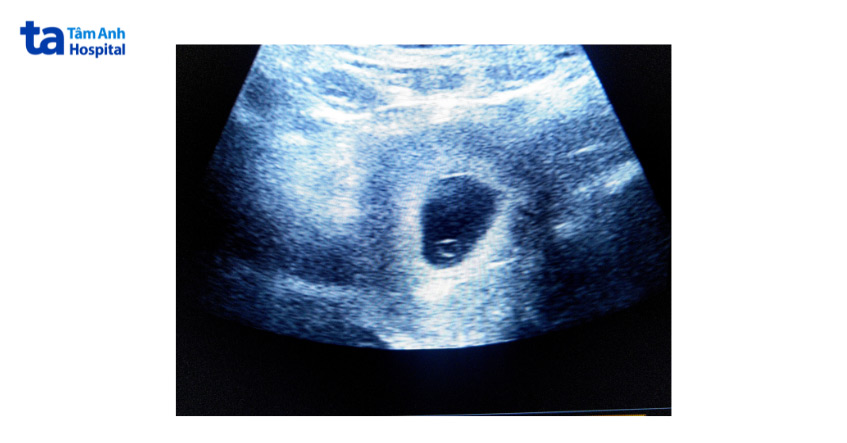

Theo bác sĩ Nguyễn Phúc Hiếu, khoảng tuần thai thứ 5 (tương đương 3 tuần sau chuyển phôi), thông qua siêu âm sẽ thấy thai khỏe mạnh, có đầy đủ túi thai và túi noãn hoàng nằm trọn bên trong. Thời điểm này, kích thước túi thai có thể đạt 18mm. Siêu âm lần đầu (khoảng 21 ngày sau chuyển phôi) nhằm xác định số lượng túi thai trong tử cung người mẹ. Bác sĩ sẽ trao đổi trực tiếp với thai phụ về cột mốc siêu âm quan trọng tiếp theo và các xét nghiệm cần thiết.

Bác sĩ Hiếu cho biết thời gian hình thành túi thai ở thai IVF tương tự với thai tự nhiên. Thông thường, khoảng tuần thai thứ 4.5-5.5, túi thai đã hình thành và thấy rõ trên hình ảnh siêu âm.

Khoảng ngày thứ 17 sau chuyển phôi, siêu âm đầu dò ngả âm đạo có thể nhận thấy túi thai với đường kính 2-3mm. Trường hợp siêu âm bụng sẽ thấy muộn hơn, khoảng tuần thai thứ 5. Mặc dù vậy, sự phát triển thai nhi không hoàn toàn giống nhau. Vì vậy nếu siêu âm lần đầu tiên (khoảng 21 ngày sau chuyển phôi) không thấy túi thai rõ ràng, vợ chồng không nên quá lo lắng. Bác sĩ sẽ chỉ định thực hiện siêu âm lại sau 1-2 tuần.